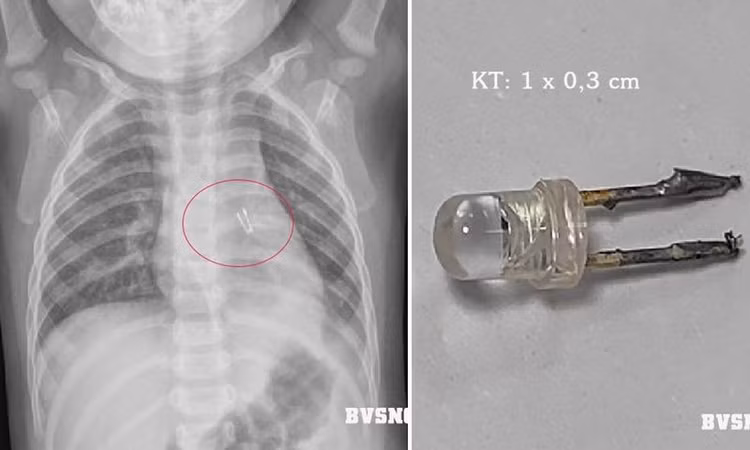

Kết quả chụp X-Quang ngực cho thấy hình ảnh dị vật cản quang quanh vị trí đoạn cuối phế quản gốc bên trái kích thước 10×3 mm. Tiến hành hội chẩn chuyên khoa với kíp nội soi, các bác sĩ quyết định chỉ định nội soi khí quản cấp cứu gắp thành công dị vật là một chiếc bóng đèn điện tử ra khỏi cơ thể trẻ.

| Gắp dị vật trong đường thở bé 10 tháng tuổi - Ảnh Bệnh viện Sản Nhi tỉnh Quảng Ninh |

Tại thời điểm nội soi, do dị vật có hai đầu cạnh sắc nhọn nên khi đi qua đã làm viêm loét, xung huyết niêm mạc khí quản, xuất hiện nhiều dịch mủ đục.